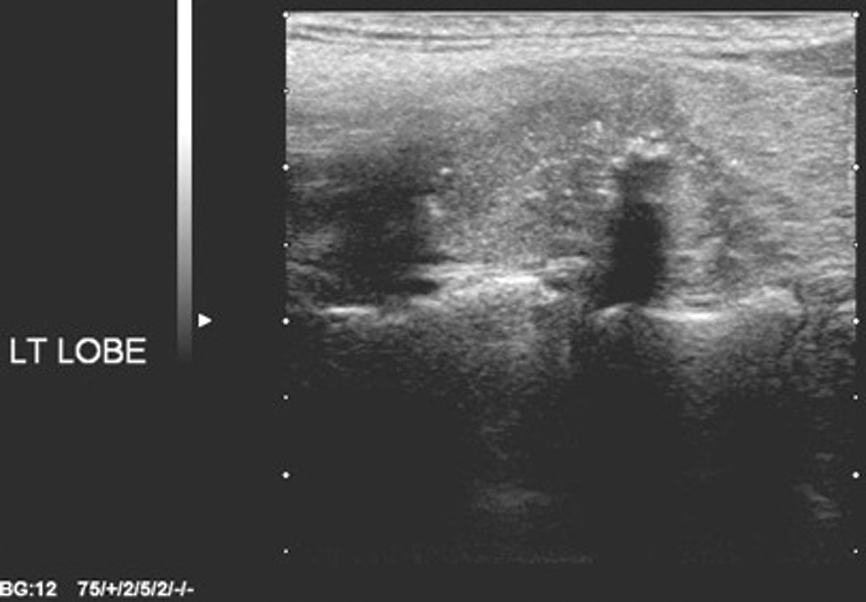

Thyroid nodules – time for a rational imaging approach

“The more you know, the harder it is to take decisive action. Once you become informed, you start seeing complexities and shades of gray. You realize that nothing is as clear as it first appears. Ultimately, knowledge is paralyzing.” Calvin,...